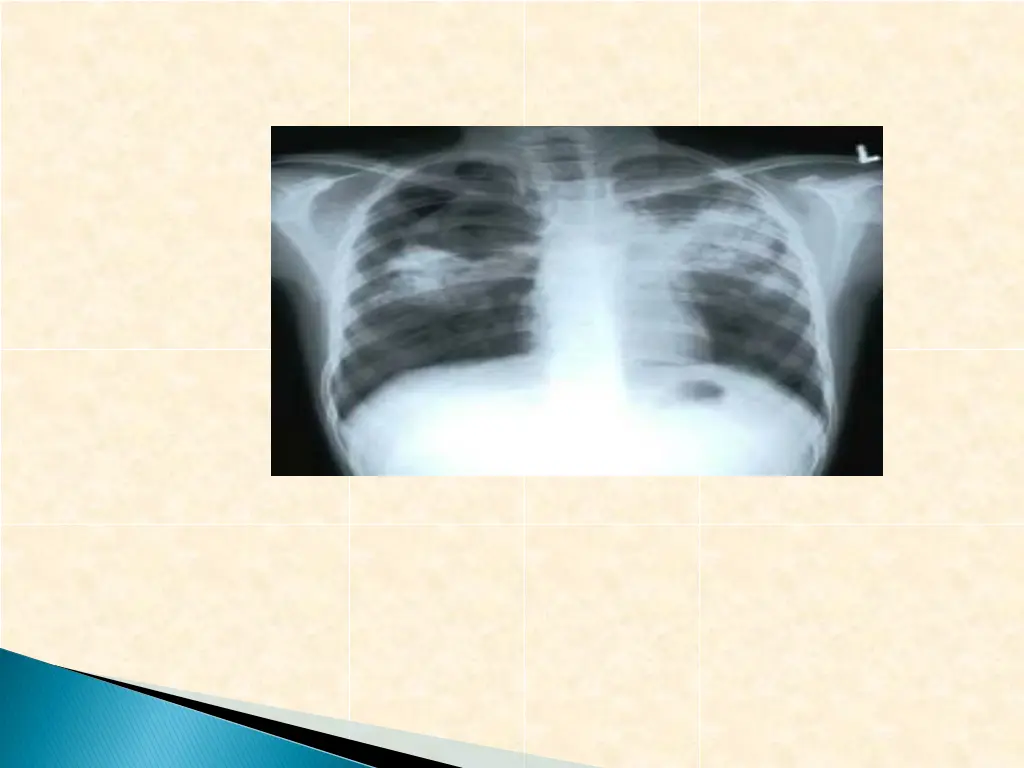

Is caused by Mycobacterium tuberculosis and other memebers of the tb complex M. tuberculosis infect one third of human race The patient usually presents with fever of long duration Symptoms of cough and coughing of blood (Haemoptoysis) when the chest is affected In some cases it present as meningitis and cerebral infection presenting with chronic neurological symptoms and signs

a) Mantoux test, Tuberculin skin test(TST) b)Chest x-ray for focus of tb infection c) CSF microscopy for AFB d) CSF culture an solid medium [L.J ]or fluid medium[MIGT] e) PCR or other molecular bioLOGY tests for presence of bacterial element tb and others f) Culture of CSF for Brucella g) Serology for Brucella Combination of these finding with clinical history and examination finding